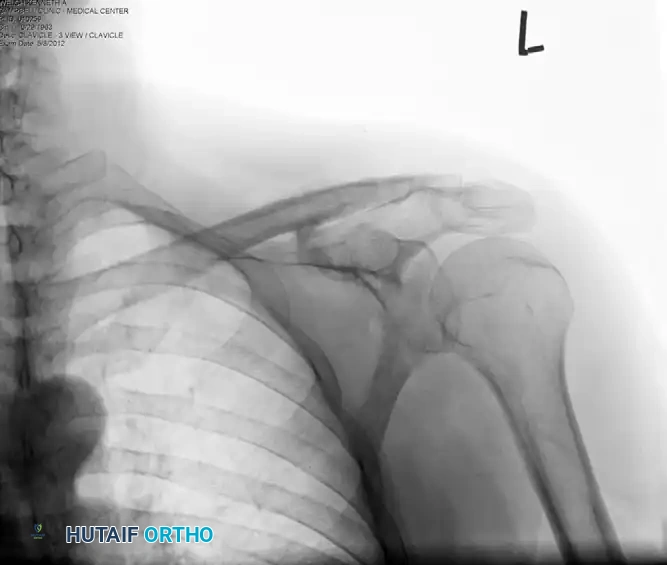

Below is a radiographic progression of a highly displaced distal clavicle fracture managed with a hook plate.

Preoperative Evaluation: Note the severe superior displacement of the proximal clavicular shaft, indicating complete loss of the coracoclavicular ligamentous restraint.